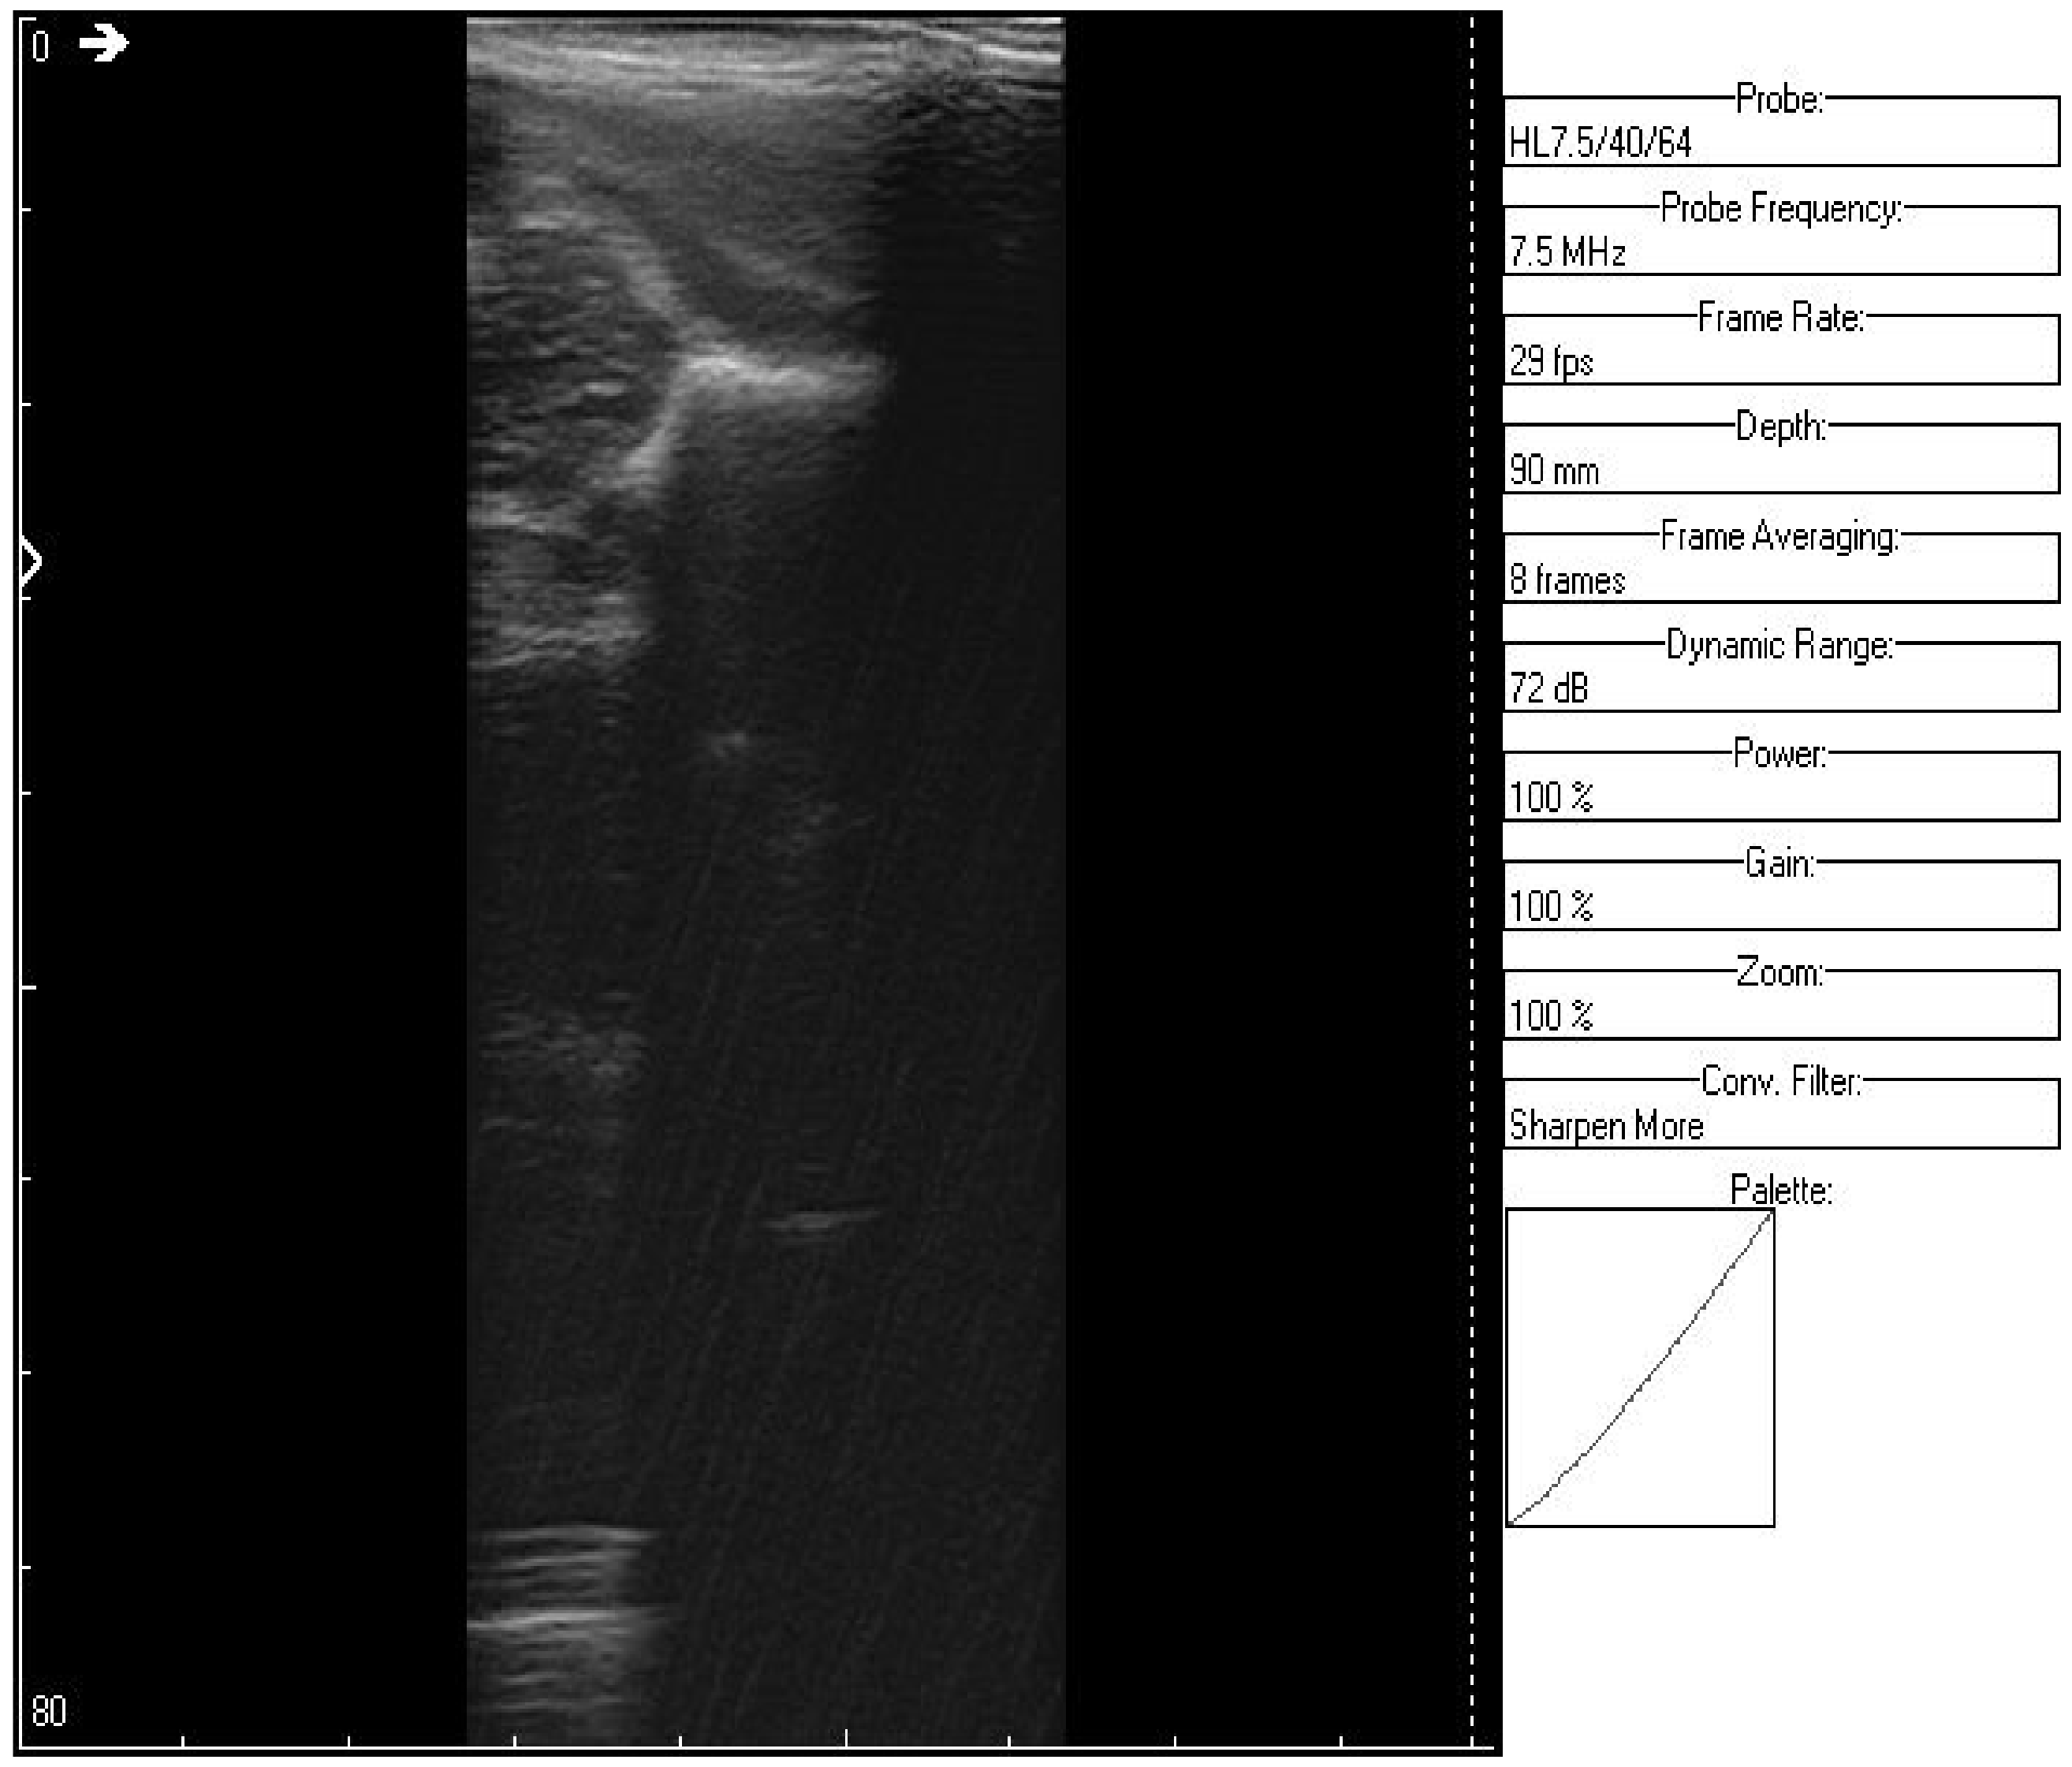

An ultrasound (Image 3 (Figure 10 and Figure 11)) was taken of a male patient with a sample frequency of 7.5 MHz and a frame rate of 29 fps. The parameters are same as in the previous two cases, yet the image of the acetabulum is hardly visible.

After applying the HWT filtering (Figure 12), the acetabulum, the femoral head, and the femur can be outlined by any physician.

We may conclude, when comparing last two images, that after filtering several details can be seen, easing the process of diagnosis for a trained physician. The denoised images are brighter and more details (not visible on the original image) can be distinguished.

Figure 10. Original data, Image 3.